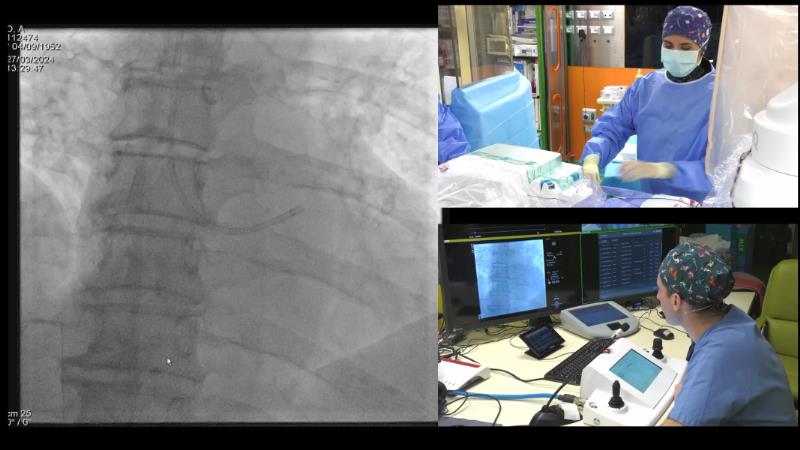

In this session, discover the effectiveness and safety of robotic PCI for both simple and complex lesions requiring additional devices like IVL, IVUS, laser, and FFR. Learn about the numerous benefits of robotics for patients and cathlab teams, including enhanced precision in wire navigation and stent positioning, full radioprotection, and reduced orthopedic injuries. Explore the growing interest in robotics within the interventional cardiology community, anticipate future technical advancements, and understand how AI will accelerate the integration of robotics and vice versa.

- To learn about a robotic PCI step-by-step from real-life experience

- To understand benefits of robotics in interventional medicine and other indications